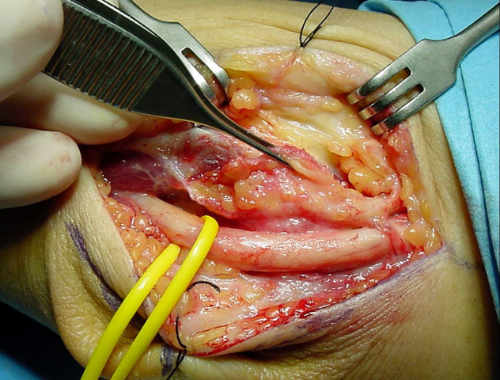

Es importante comprobar una vez liberado el nervio que no se subluxa. (Fig. 5).

Fig. 4: Liberación in situ del nervio

Fig. 5: Comprobación en flexión de la ausencia de subluxación del nervio

En estos casos optamos por realizar una mínima resección de la epitróclea y recubrimiento con fascia (epitroclectomía más epitrocleoplastia) (figuras 6 y 7), porque no devasculariza al nervio tanto como las transposiciones nerviosas, dejando éstas para las recidivas o deportistas profesionales de lanzamiento (béisbol, jabalina…) (figura 8).